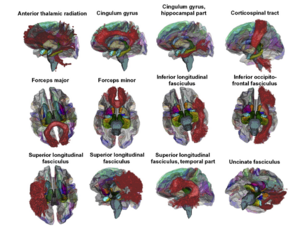

Seeing More by Showing Less: Orientation-Dependent Transparency Rendering for Fiber Tractography Visualization

Publication: PLoS One. 2015 Oct 7;10(10):e0139434. PMID: 26444010 | PDF Authors: Tax CM, Chamberland M, van Stralen M, Viergever MA, Whittingstall K, Fortin D, Descoteaux M, Leemans A. Institution: Image Sciences Institute, University Medical Center Utrecht, Utrecht, The Netherlands. Background/Purpose: Fiber tractography plays an important role in exploring the architectural organization of fiber trajectories, both in fundamental neuroscience and in clinical applications. With the advent of diffusion MRI (dMRI) approaches that can also model "crossing fibers", the complexity of the fiber network as reconstructed with tractography has increased tremendously. Many pathways interdigitate and overlap, which hampers an unequivocal 3D visualization of the network and impedes an efficient study of its organization. We propose a novel fiber tractography visualization approach that interactively and selectively adapts the transparency rendering of fiber trajectories as a function of their orientation to enhance the visibility of the spatial context. More specifically, pathways that are oriented (locally or globally) along a user-specified opacity axis can be made more transparent or opaque. This substantially improves the 3D visualization of the fiber network and the exploration of tissue configurations that would otherwise be largely covered by other pathways. We present examples of fiber bundle extraction and neurosurgical planning cases where the added benefit of our new visualization scheme is demonstrated over conventional fiber visualization approaches. Funding:

|